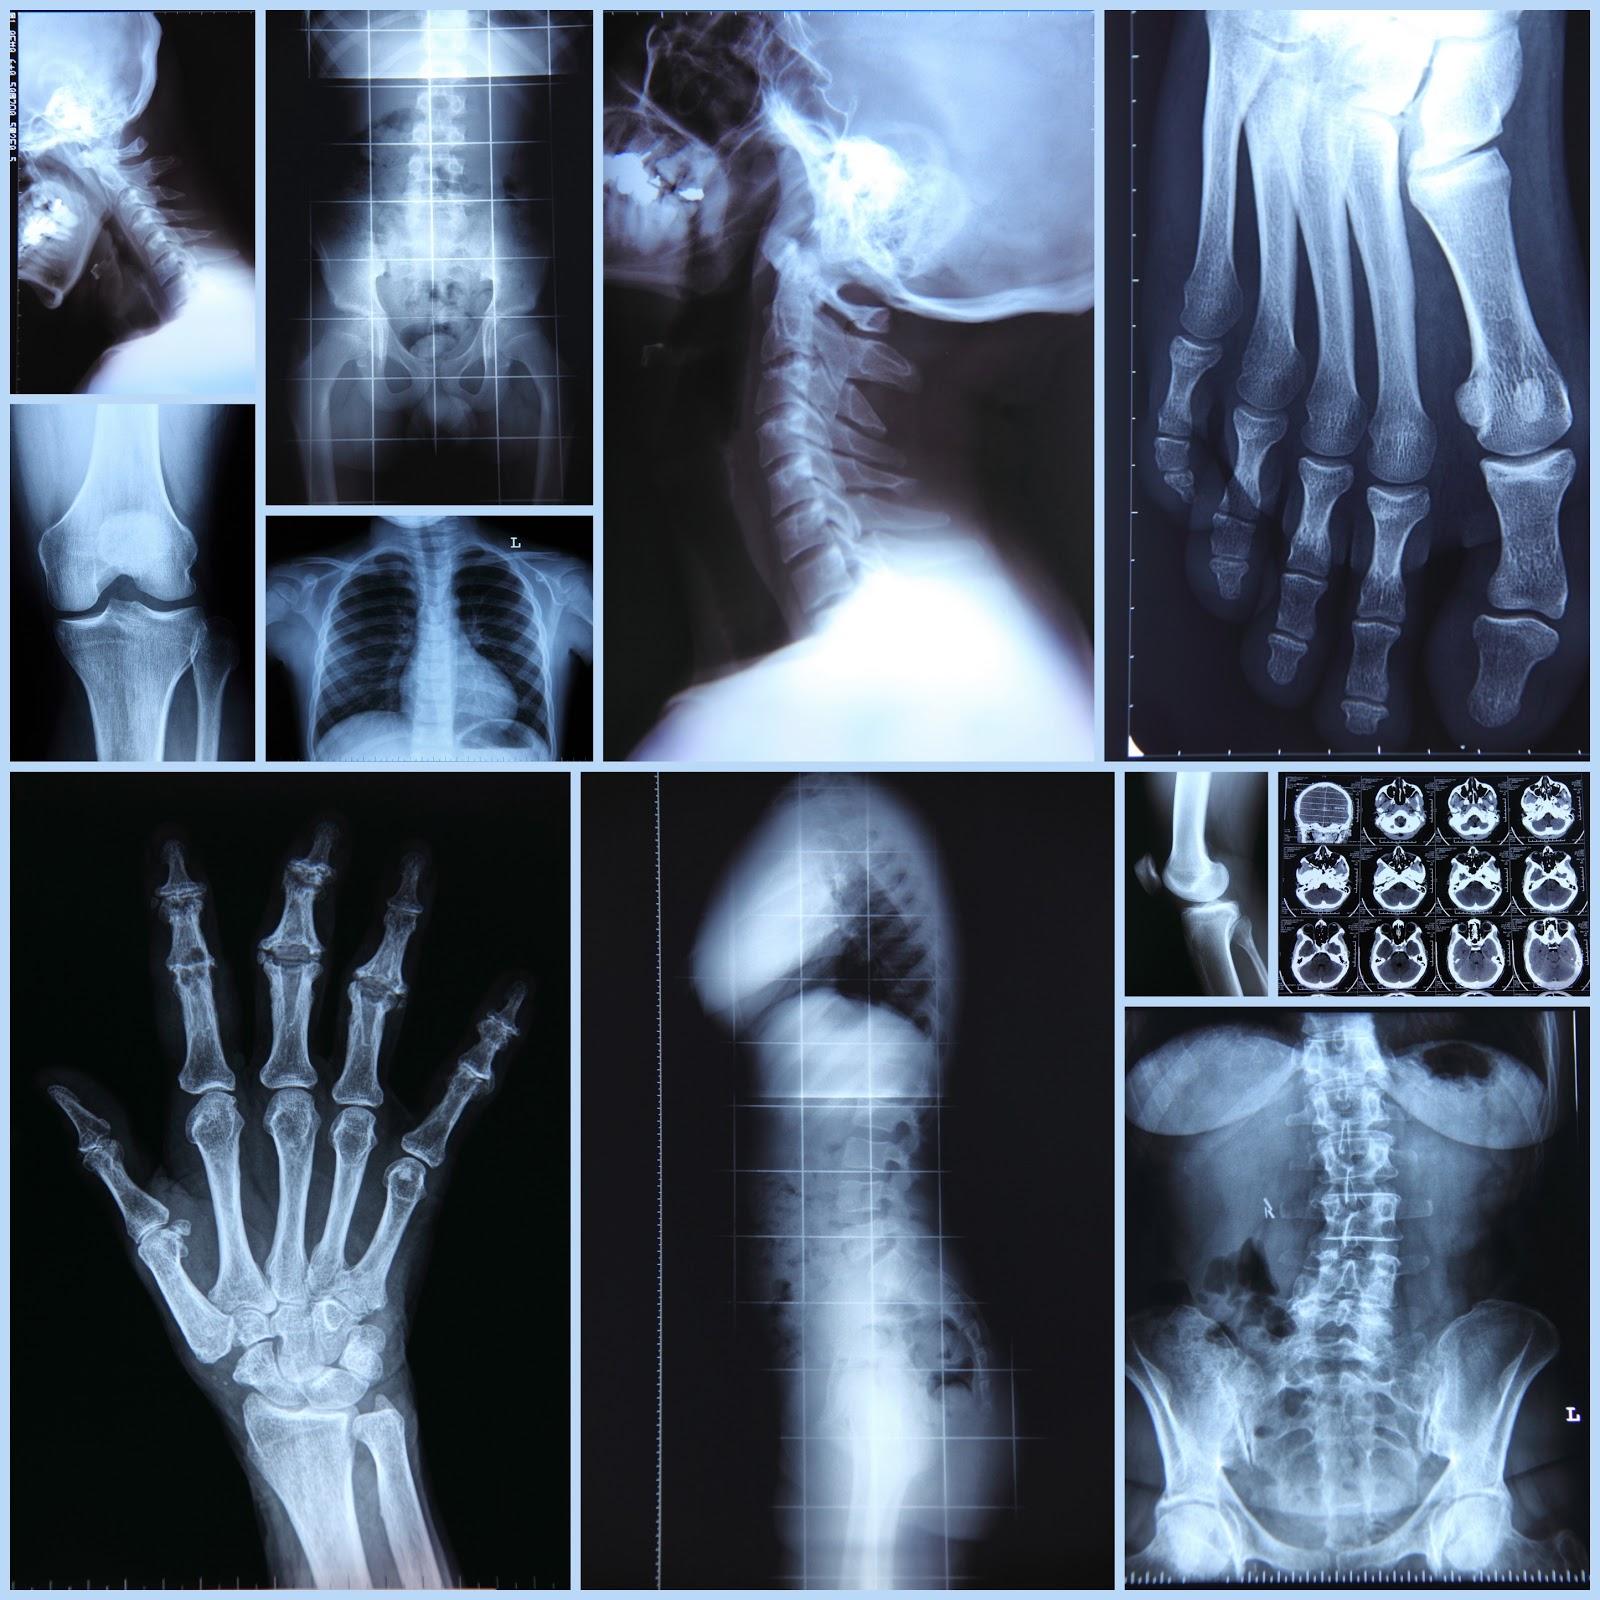

Рентгеновский эффект создает фантастические композиции в этих фотографиях девушки, чье тело становится прозрачным, демонстрируя скелет и внутренние органы. Она позирует в разных позах, ее силуэт светится загадочным свечением. Каждый кадр передает атмосферу научной фантастики и медицинского искусства. Ее кожа кажется полупрозрачной, позволяя увидеть кости и мышцы. Фотографии рассказывают о хрупкости человеческого тела и его внутренней красоте. Девушка то стоит в задумчивости, то делает грациозное движение. Эти иллюстрации вдохновляют на размышления о человеческой анатомии и уязвимости. Каждая картинка - это момент прозрения, когда внешнее уступает место внутреннему. Девушка воплощает образ современной Медузы, сочетающей красоту и загадочность.

Сквозь материю: тайны анатомии